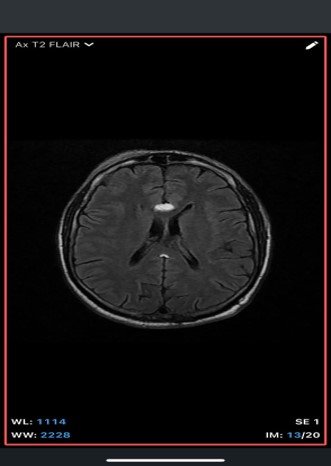

An extra-axial TI/T/Flair hyperintense lesion in midline at the inferior edge of the interhemispherie fissure extending along the superior margins of the corpus callosum with areas of blooming consistent with calcification and no post contrast enhancement –likely pericallosal lipoma.

• MRI

• T1-weighted: Hyperintense (fat signal).

• T2-weighted: Variable, usually hyperintense; may show chemical shift artifacts.

• Fat-suppressed sequences: Complete signal suppression confirms fat composition.

• Post-contrast: No enhancement.